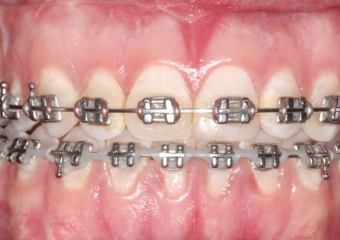

Mordida inicial - Clínica Cliniface

Mordida inicial